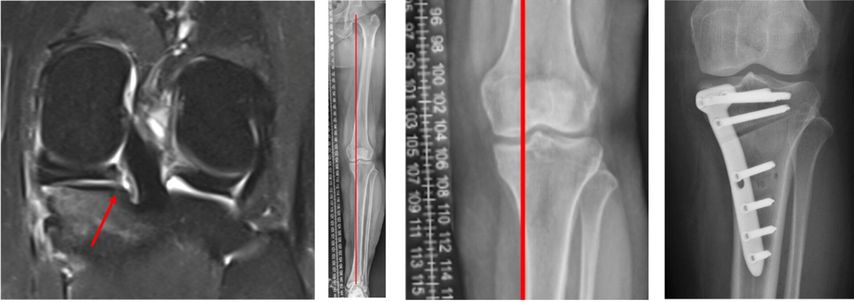

Dies verdeutlicht der Fall einer 46 Jahre alten Patientin mit atraumatischen Schmerzen im medialen Kniegelenk links (Abb. 2). In der präoperativen MRT-Diagnostik zeigt sich der degenerative Innenmeniskuswurzelriss (linkes Bild, Pfeil). In der präoperativen Röntgen-Ganzbeinaufnahme im Stehen ist ein Varus-Malalignment von 4° zu erkennen (Bilder in der Mitte). Es erfolgte eine arthroskopische Innenmeniskuswurzelrefixation mittels transtibialer Auszugsnaht, kombiniert mit einer valgisierenden medial öffnenden hohen tibialen Osteotomie (rechts).

Risiko Meniskusriss mit Achsenfehlstellung

Abweichungen von der Beinachse und Verlust des Meniskus erhöhen beide gemeinsam das Risiko für eine Arthrose. «Wir haben speziell für Meniskusrisse bisher keine belastbare Evidenz, ab wann man die Beinachse operativ korrigieren sollte», sagte Behrendt. Eine Ausnahme scheinen Wurzelverletzungen zu sein. In einer Studie aus Seoul17 mit 476 Patienten, die wegen einer Pathologie am Innenmeniskus arthroskopiert wurden, hatten diejenigen mit Wurzelläsion eine deutlich ausgeprägtere Varusfehlstellung als Patienten mit anderen Rissformen (4,5±3,4° versus 2,4±2,7°). Orthopäden von der Mayo Clinic in Rochester18 empfehlen, bei Meniskuswurzelrissen nach einem Algorithmus vorzugehen (Abb.2). Viele Jahre wurde eine Achsenfehlstellung von >5° als korrekturbedürftig angesehen. Auf Grundlage einer Studie von 201319 und von Daten aus dem Knorpelregister der DGOU20,21 empfiehlt die Arbeitsgemeinschaft Klinische Geweberegeneration der DGOU, die Beinachse bereits ab einer Fehlstellung von 3° zu korrigieren.22 Eine Beinachsenkorrektur sei immer eine sehr individuelle Entscheidung, über die der Patient gut aufgeklärt werden müsse, sagte Behrendt.«Bei der Weiterentwicklung einer bereits eingetretenen Arthrose spielt die Achse einen sehr entscheidenden Einflussfaktor. Dies sollte grosszügig mit in das diagnostische Workup integriert werden.»